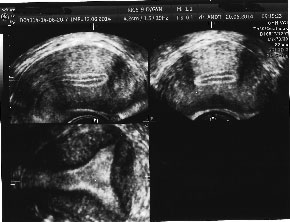

![]() | ![]() |

| Cavitate uterina sever afectata postembolizare uterina. Arhiva personala Dr. Lara Andronescu | Cavitate uterina sever afectata postembolizare uterina. Arhiva personala Dr. Lara Andronescu |